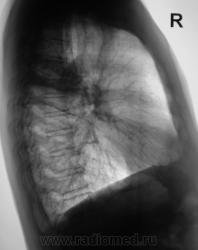

Произведена рентгенограмма в прямой стандартной проекции и томограммы в стандартных срезах.

«Пневмония», сразу показалась какой-то «фердиперсовой», с учетом лечения в стационаре ранее, довольно хорошего самочувствия пациента и наличием весьма «убогой» клиники. После проведения исследования было рекомендовано провести противовоспалительное лечение, исследование мокроты с целью проведения дифференциальной диагностики, рекомендована консультация фтизиатра.

Мы в протоколе, конечно, отметили, о возможности инфильтративного туберкулёза, д/д ряд даже не дали.

Коллега фтизиатр кричит, что «это не мое», говорит об определенной динамике по рентгенограммам и томограммам, опирается на наличие воздуха в бронхах (воздушная бронхограмма), гнет линию в сторону пневмонии. Да, его коллегу, тоже можно понять, ибо, давно «план» по выявлению выполнили и даже перевыполнили, его тоже, по всей видимости, за выход за «рамки плана» по голове -то не погладят.

Но, мы стойко несмотря ни на что, стояли на тубере.

Пациент 4 месяца, по полной программе отлежал в областной конторе, ЦВК утвердило «инфильтративный». После выписки был направлен под надзор фтизиатра по месту жительства. Ниже иллюстрации после выписки.

Снимки сегодня.